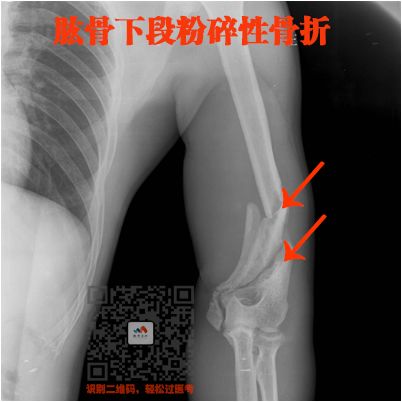

四、长骨骨折

就是四肢的长骨骨折

上肢:

肱骨、尺骨、桡骨

下肢:

股骨、股骨头、胫骨、腓骨

骨折非常简单的

这里就不讲解了,大家看片就行

看片